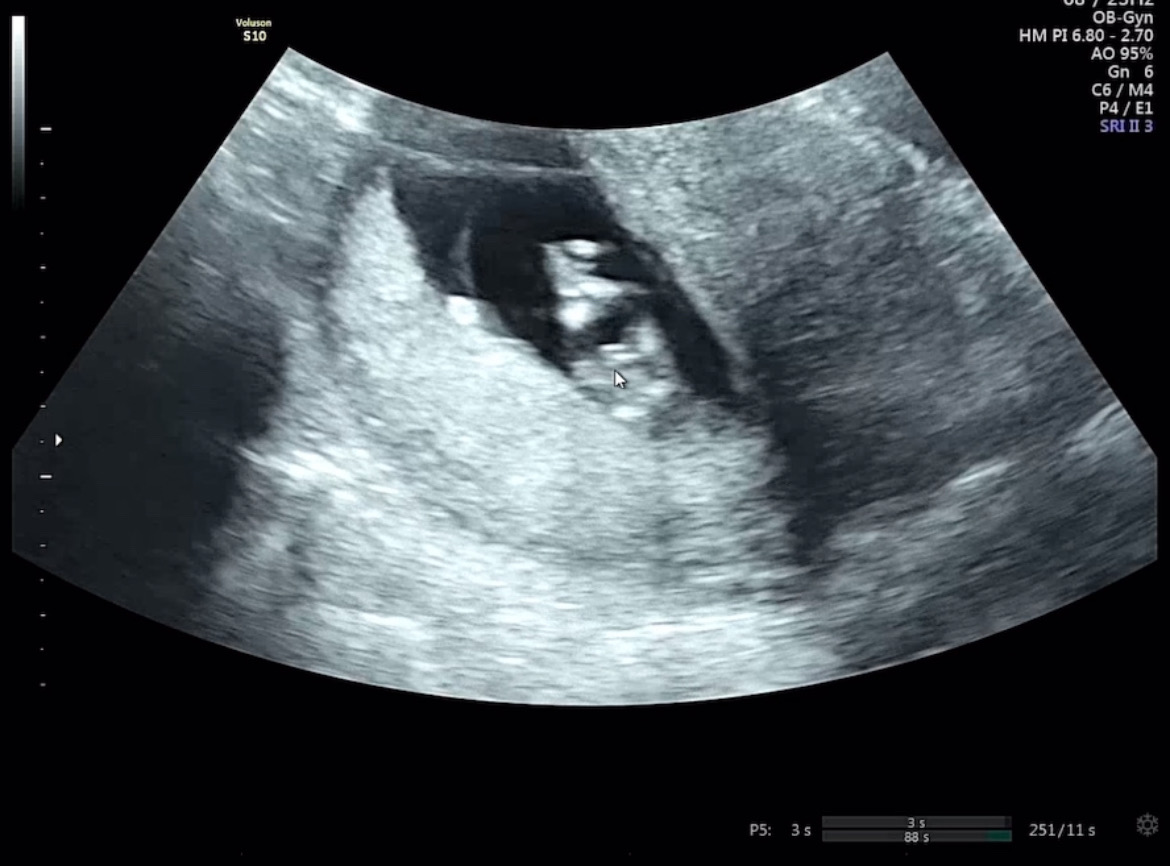

12주차 성별 반전 있을까요ㅎㅎ?

주수는 12주 0일이에요~ 발 꼬고 있는 다리사이 초음파인데요 의사선생님이 다리사이에 뭐가 보이는 것이 아빠를 좀더 닮을 가능성이 커보인다고 하셨는데 정확한건 16주에 다시 보자고 하셨어요! 아들일까요ㅎㅎ?